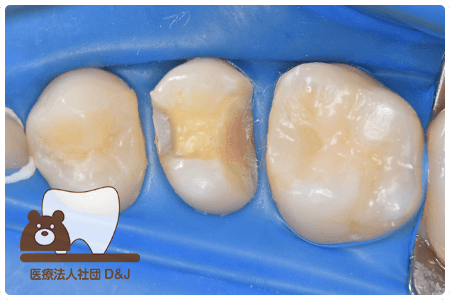

症例8フルジルコニアクラウン

治療前

治療中

治療後

治療前

治療中

治療後

29歳 女性

- 治療内容

- 銀歯からフルジルコニアクラウンへの修復

- 治療期間

- 根の治療含め3か月

- 費用

- 自費

フルジルコニアクラウン:77,000円(税込)

- その他の治療の費用は含まれておりません。

- リスク・副作用

- 強い衝撃が加わると欠けたり割れたりする可能性があります。また、噛み合わせの状態によっては脱離や周囲の歯への影響が出ることもあります。